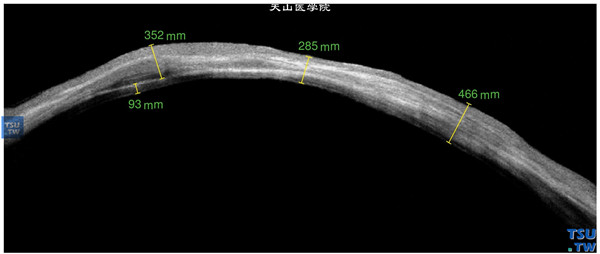

结角膜干燥:左眼,角膜薄厚不均,角膜基质浑浊,可见致密的、密度不均的影像,可见血管膜在角膜表面的影像和深度